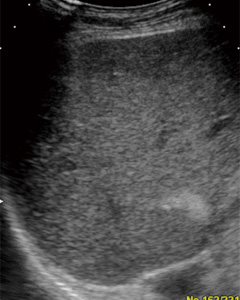

気泡である超音波造影剤ソナゾイドは,送波音圧を低めに設定することで超音波による気泡の破壊を極力低減し,気泡からの反射波に含まれるハーモニック成分を画像化する。WPIは,従来のPulse Inversion法より低周波成分を強調しつつ,効率良くハーモニック成分を抽出する手法で,これにより高感度とペネトレーションの改善を図っている。

図2 オルタネートモード (画像ご提供:三重大学 田中秀明先生)

a:WPI像

b:LowMIでのFundamental像